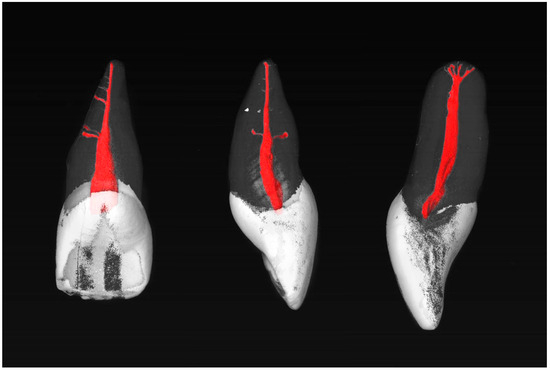

The maxillary central incisors were scanned in a desktop µCT unit (μCT; SCANCO Medical AG, Brüttisellen, Switzerland) at 70 kV and 114 mA, generating a total of 800 to 1200 cross-sectional images per tooth. To visualize the root canal anatomy, the cross-sectional images were reconstructed in three dimensions using VGSTUDIO Max 2.2 software (Volume Graphics GmbH, Heidelberg, Germany) and displayed in different colors. The pulp chamber and root canal system were colored red, the enamel was colored white, and the dentin was displayed transparently, thus enabling optimal assessment. The root canal anatomy was evaluated in accordance with the classification system proposed by Briseño-Marroquín et al. [28]. This classification employs a four-digit code that subdivides the root canal structure into three sections: coronal, medial, and apical. The fourth digit indicates the number of main foramina with a diameter of at least 0.2 mm. Accessory root canals were defined as additional canals that do not originate from the same main canal at the apical end and whose diameter is less than 0.2 mm [28]. The root canal configuration, accessory canals, and accessory foramina were evaluated in both relative and absolute numbers.

Most commonly, the MxCIs had no accessory apical foramina (85.7%). One (8.0%), two (3.6%), three (0.9%), or four (1.8%) could be observed (diameter > 0.1 mm). Examples of the MxCI specimens are shown in Figure 1 and Figure 2.

µCT images of maxillary central incisors with a 1-1-1/1 RCC (left) and 1-1-1/2 RCC (center) without accessory canals, and a 1-1-1/1 RCC (right) with two accessory canals in the middle root third.